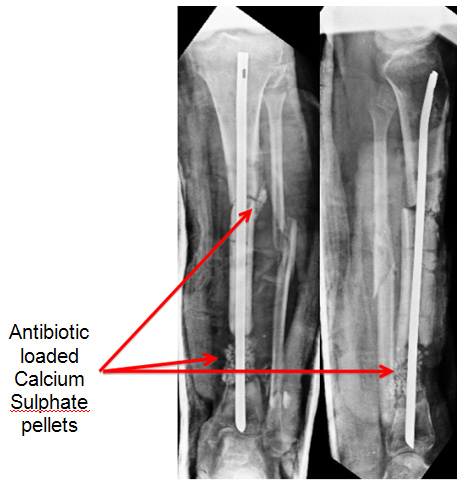

In surgery the dead bone (sequestrum) & all the infective tissue was removed. An intra-medullary V-nail was applied to keep the bone aligned and antibiotic loaded calcium sulphate pellets were instilled in the proximal and distal fracture sites to control infection. | ||

| The calcium sulphate pellets are completely absorbed. The infection is settled and the sinuses healing well. The upper fracture is showing signs of healing. | ||